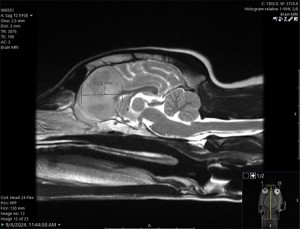

In August, Geddy began having seizures, and her veterinarian referred the eight-year-old to Penn Vet for further evaluation. At Penn Vet’s Ryan Hospital, Tessa Arendt, DVM, specialty intern in Neurology, and Wojciech Panek, DVM, DACVIM, assistant professor of neurology and neurosurgery in the Department of Clinical Sciences and Advanced Medicine, performed a brain MRI, which revealed a right frontal lobe mass.

“An MRI doesn’t always tell us exactly what we’re dealing with even though it allows us to see the tumor,” said Panek. “Based on Geddy’s tumor imaging characteristics, we suspected a glioma — an aggressive brain tumor.”

“The technology created a hologram from Geddy’s initial MRI, which was really helpful for procedure planning and for navigating hard-to-see areas,” said Panek. By superimposing Geddy’s MRI images with anatomical accuracy onto Geddy’s skull, the surgeons were able to first biopsy and then debulk the tumor.

The following day, Geddy was awake and charming her care team. Soon after, they discharged her with medication to manage inflammation and prevent seizures. A follow-up a few weeks later showed she was healing well, and a November MRI indicated no radiological signs of tumor regrowth.